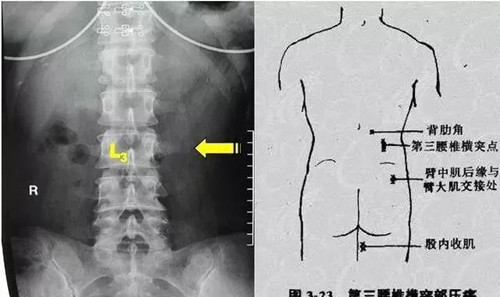

1.什么是“腰三橫突綜合征”?

簡(jiǎn)單來說,就是腰三橫突周圍軟組織發(fā)生無菌性炎癥,引起腰臀部疼痛的一種綜合癥候群。

總的來講就是腰三橫突周圍組織發(fā)生無菌性炎癥,出現(xiàn)局部組織粘連、變性及增厚等。